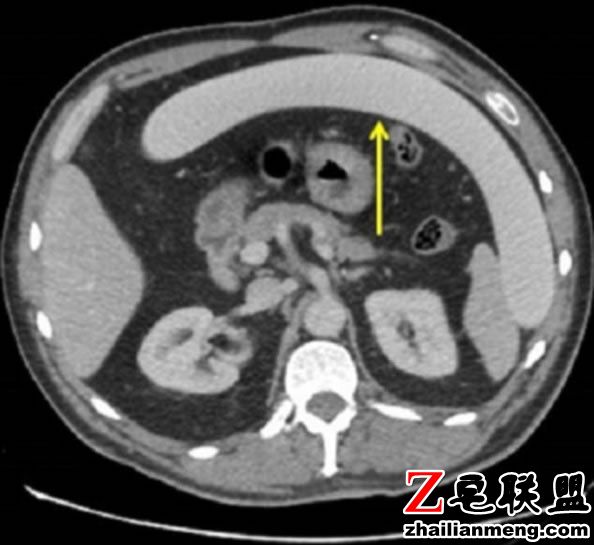

医生Saad Ikram 与团队诊治后表示,通过X 光发现,这个长达77厘米的“U形物”,在该男子的下腹部呈现不可思议的情况,更让他的肠子穿刺破裂。

医生随后为他进行手术,并先切掉被刺烂的20公分大肠,再进行截肠造口术,防止排泄物在身体乱窜,术后9天的他,都必须采管灌进食。